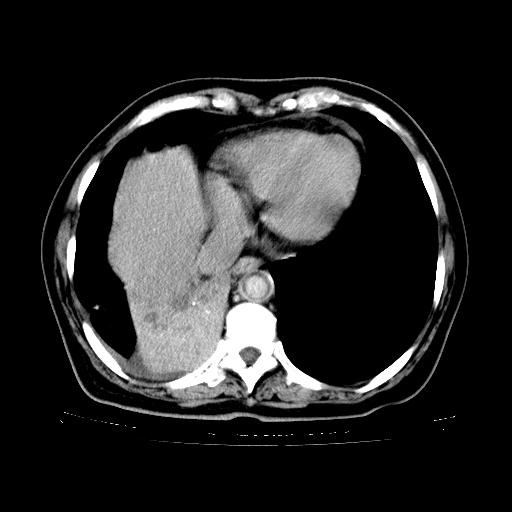

标题: CT23067:女,70岁,咳嗽、咳痰一个月,低热一周。 [打印本页]

女,70岁,咳嗽、咳痰一个月,低热一周。

1.左上肺结核,部分纤维化。右肺中下叶部分肺不张,内见液化、坏死及点状钙化,右中下叶支气管壁增厚、管腔狭窄,见多个点状钙化,结合临床考虑支气管内膜结核,建议痰检查抗酸杆菌并参考血沉。两肺多个小圆点状高密度灶,境界模糊,多考虑结核肺内播散。但本人年龄较大首先应支气管镜检以除外右肺癌。

2.胸主动脉夹层。

支持,首先一元论解释。胸主动脉部分层面环形低密度,中心强化。环形影不强化。不象真假腔的改变。我考虑动脉炎,不太支持夹层动脉瘤-和大家的观点不一致,希望楼主让患者再做个心血管的彩超吧。